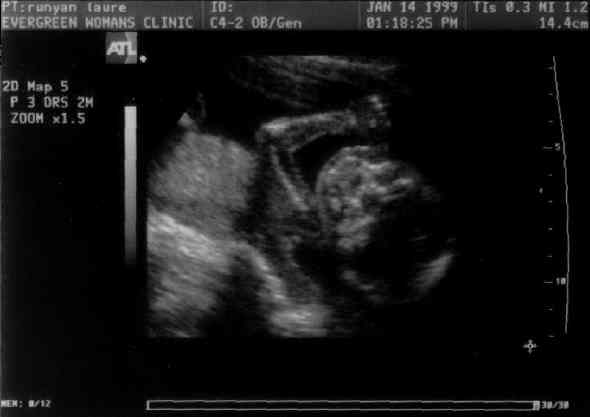

Baby demonstating superior arm strength.